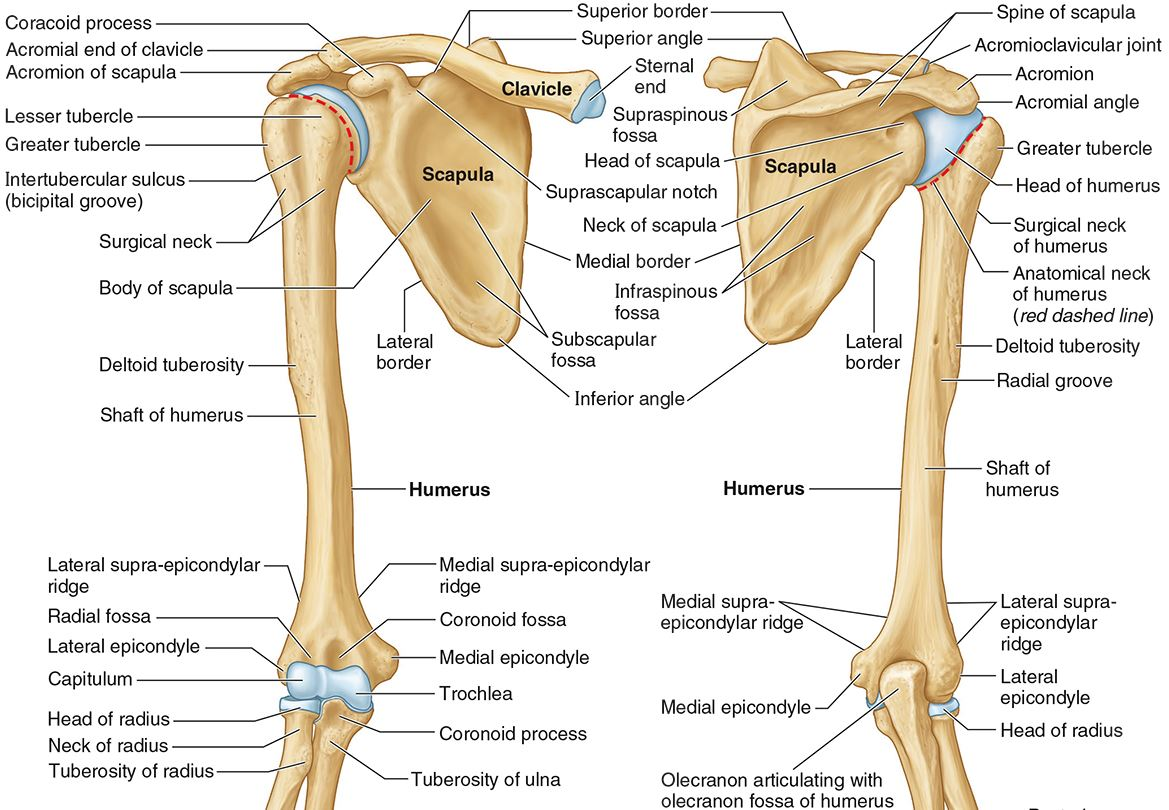

What part of the humerus is this?

The head of the humerus articulates with the scapula at the glenohumeral joint.

What part of the humerus is this?

The anatomic neck is an indentation distal to the head and provides an attachment for the fibrous joint capsule of the glenohumeral joint.

What part of the humerus is this?

The greater tubercle lies lateral and distal to the anatomic neck.

What part of the humerus is this?

The lesser tubercle lies on the anterior/medial side of the humerus, just distal the anatomic neck.

What part of the humerus is this?

The intertubercular (bicipital) groove lies between the greater and lesser tubercles.

What part of the humerus is this?

The surgical neck is a narrow area distal to the tubercles. It is a common site for proximal humerus fractures.

What part of the humerus is this?

The humeral shaft features the deltoid tuberosity laterally for the distal insertion of the deltoid muscle.

What part of the humerus is this?

The radial groove is an oblique depression that contains the radial nerve and deep brachial artery.

Which parts of the humerus is this?

The medial and lateral epicondyles are distal prominences to which many forearm tendons attach, near the elbow joint.

Which parts of the humerus is this?

The medial and lateral supracondylar ridges extend superiorly from the medial and lateral epicondyles.

Which parts of the humerus is this?

The trochlea and the capitulum (the condyles) are the most distal surfaces of the humerus, where it articulates with the forearm bones at the elbow joint

What part of the humerus is this?

The olecranon fossa is a posterior depression above the trochlea that receives that olecranon process of the ulna

What part of the humerus is this?

The coronoid fossa is an anterior depression above the trochlea that receives that coronoid process of the ulna.